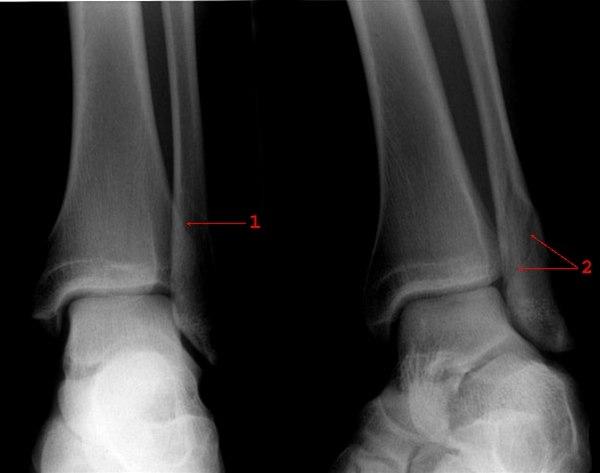

Frontal- og skråprojeksjon av venstre ankel

Skråfraktur (1 og 2), uten feilstilling gjennom laterale malleol

Frakturen er best synlig i skråprojeksjon (2)